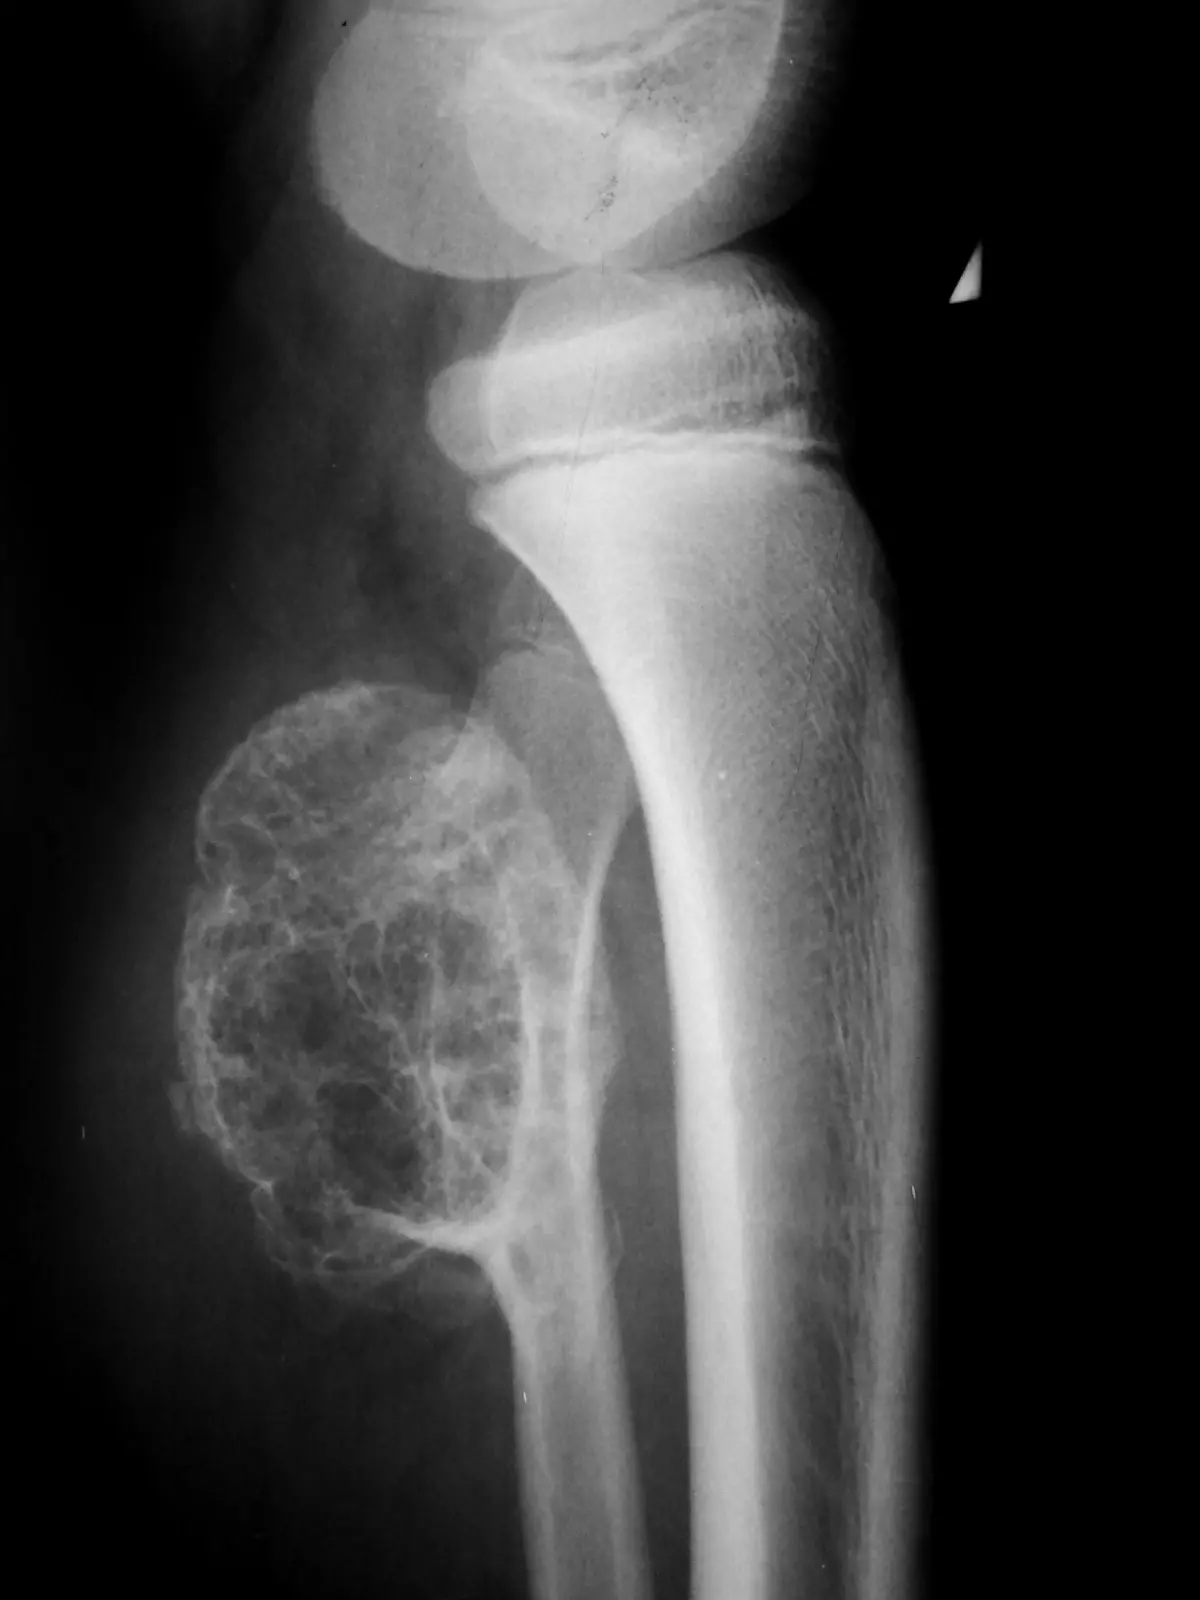

Доброкачественные опухоли костей, такие как:

- Остеобластома;

- Остеоид-остеома;

- Хондромиксоидная фиброма;

- Остеохондрома.

Вышеперечисленные доброкачественные новообразования также могут вызывать выраженный болевой синдром в костях при крупных размерах опухоли.